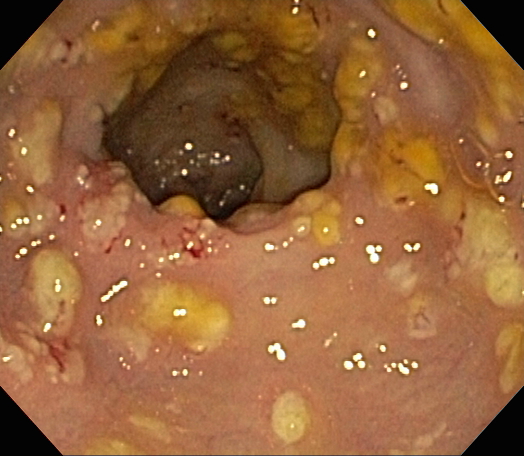

내시경 사진, S상 결장 벽에서 노란색 가성 막이 보이는 가성 막 대장염

''C. difficile'' 독소를 검출하는 검사가 나오기 전에는, 결장경 검사나 S상 결장경 검사를 통해 진단하는 경우가 많았다. 결장 또는 직장 점막에서 "가성 막"의 출현은 이 질환을 시사하지만, 진단적인 것은 아니다.[46] 가성 막은 염증성 잔해물과 백혈구로 구성된 삼출물로 이루어져 있다. 현재도 결장경 검사 및 S상 결장경 검사가 사용되기는 하지만, 현재는 ''C. difficile'' 독소 존재 여부를 검사하는 대변 검사가 진단의 첫 번째 단계로 자주 사용된다. 일반적으로 독소 A와 독소 B 두 가지만 검사하지만, 이 균은 다른 독소도 여러 개 생성한다. 이 검사는 100% 정확하지 않으며, 반복 검사에도 위음성률이 상당하다.[47]